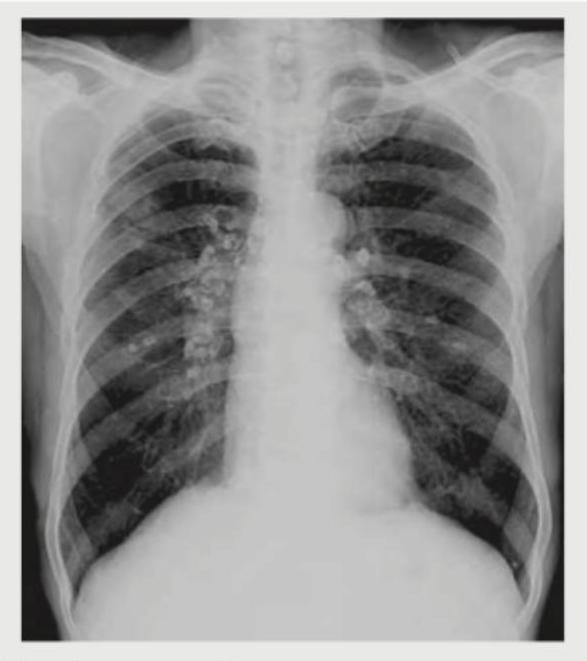

A 35-year-old lady presents with fever, skin rash and dyspnea on exertion for last 2 months. Her chest X-ray is shown below. What is the most likely diagnosis?

Explanation: ***Sarcoidosis*** - The CXR shows **bilateral hilar lymphadenopathy** and **prominent reticulonodular infiltrates**, which are classic findings in sarcoidosis. - The patient's symptoms of **fever, skin rash, and dyspnea on exertion** are consistent with systemic manifestations of sarcoidosis, a multi-organ granulomatous disease. *Shrinking lung syndrome* - Characterized by **reduction in lung volumes** usually associated with systemic lupus erythematosus, which is not suggested by the CXR findings. - The image does not predominantly demonstrate reduced lung volumes, but rather prominent infiltrates and lymphadenopathy. *Rheumatoid lung* - While rheumatoid arthritis can cause various lung manifestations (e.g., nodules, interstitial lung disease, pleural effusions), massive **hilar lymphadenopathy is uncommon**. - The clinical presentation does not include features commonly associated with rheumatoid arthritis, such as **joint pain and swelling**. *Desquamative interstitial pneumonitis* - This condition is typically associated with **smoking** and presents with patchy ground-glass opacities, not the prominent hilar lymphadenopathy seen here. - Clinical symptoms often include **cough and dyspnea**, but less commonly fever and skin rash as primary complaints, and the key imaging features are different.